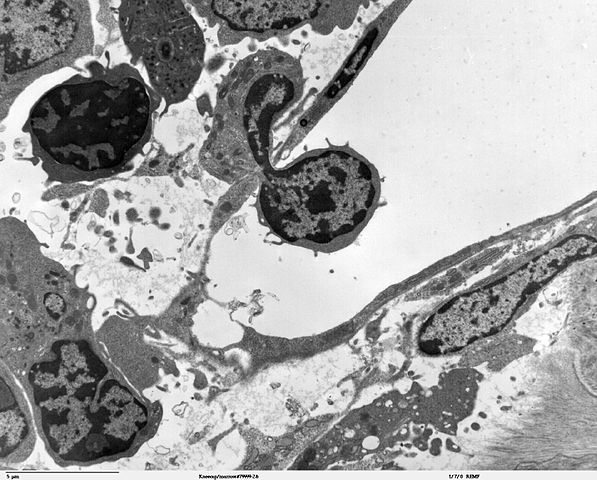

Transmission electron micrscope image of a thin section cut through an area of bone marrow area near the cartilage/bone interface in a mouse kneecap. Image shows small opening in the thin endotheliun of the vascular sinus wall, where a blood cell is crossing the thin vascular sinus wall and into the sinus lumen. JEOL 100CX TEM |